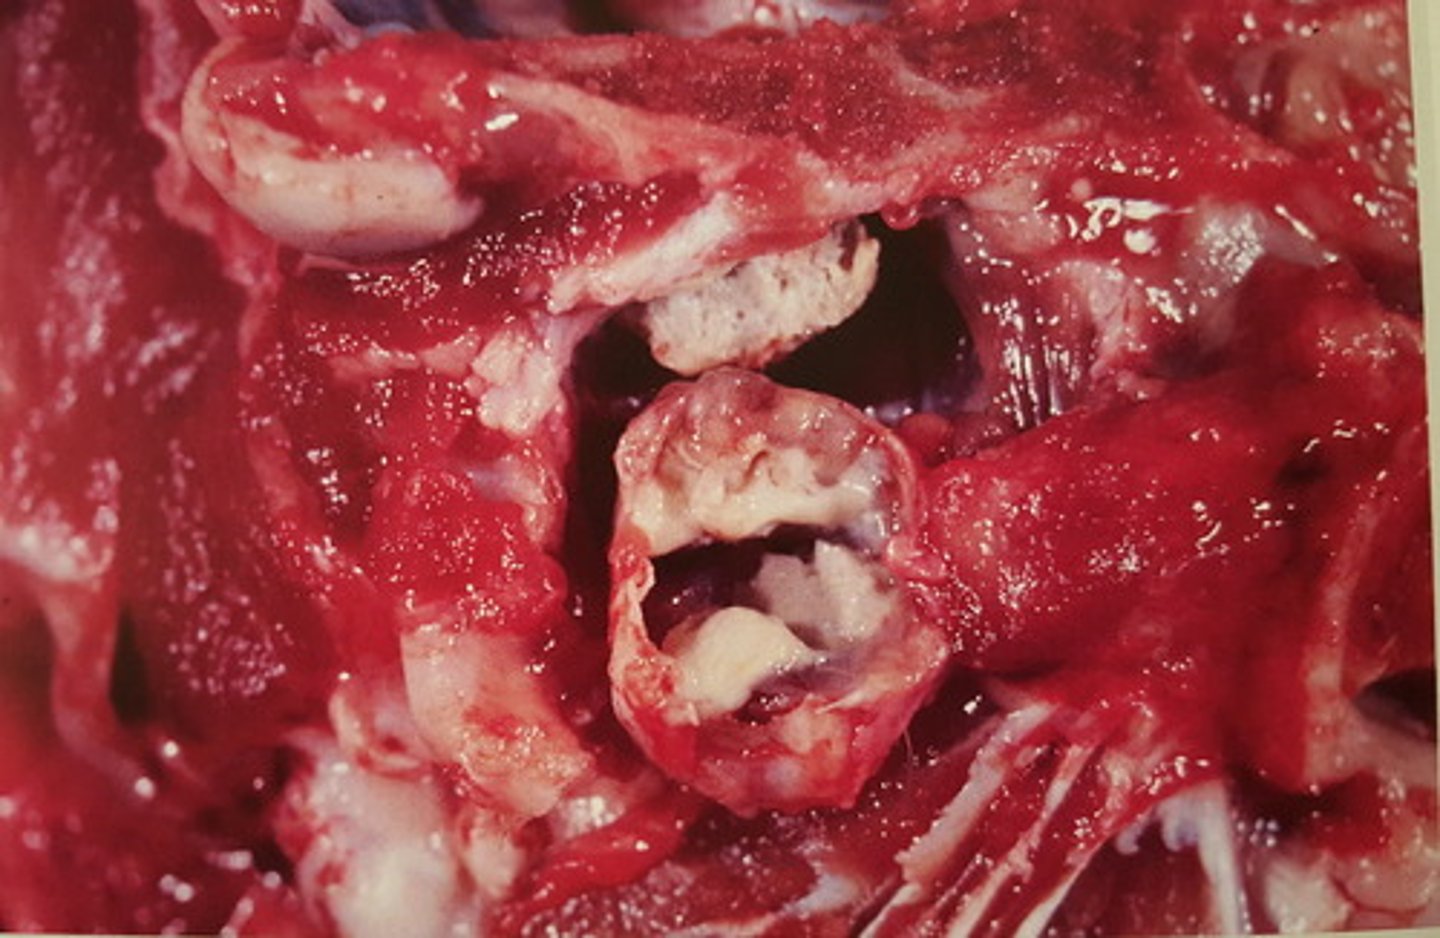

Kronisk thromboserende endophlebitis med absces formation.

Opbrud af leverabsces til venen.

Lever fra kvæg m. v. heptatica, hvad er den patoanatomiske diagnose?